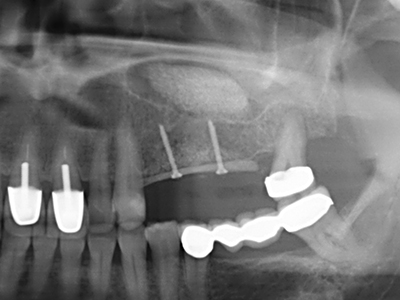

Пиезохирургията има допълнителни предимства при събиране на костни блокове. В допълнение към високата прецизност при остеотомията, описана по-горе, употребата на фините режещи накрайници значително намаляват загубата на материал. Голяма загуба на материал по време на събиране може да се очаква с дебелите накрайници, особено при употреба на борери Линдеман (Lakshmiganthan, Gokulanathan et al. 2012). Базалното разделяне, което е необходимо, особено за присадка на блок при ретромолар, е улеснено от специално създадени правоъгълни триони. В резултат на това, пиезохирургията е разглеждана като прецизна, улеснена и безопасна процедура за събиране на костни блокове в ретромоларното пространство (Happe 2007) (Фиг. 1-12).

Когато се извършват хирургични процедури върху кост в непосредствена близост до чувствителни структури като кръвоносни съдове или нерви, ротиращите инструменти създават значителен риск за ятрогенно нараняване. Пиезоелектрическите апарати могат да бъдат от помощ при препарация на костно покритие и отстраняване на твърда кост близо до нерви, особено за оголване на нервите след ятрогенно нараняване, както и по време на латерализация на нервите за резекционни и реконструктивни процедури или поставяне на имплант (Фиг. 17-20). Лекият контакт между пиезонакрайника и нерва по принцип не води до нараняване, но ако действате непредпазливо с трионообразни движения или приставки за остатъчен костен субстрат, може да причините временно или перманентно увреждане на нерва. Въпреки това, рискът от увреждане се счита за много по-малък, отколкото при употреба на триони или ротиращи инструменти (Pereira, Gealh et al. 2014).